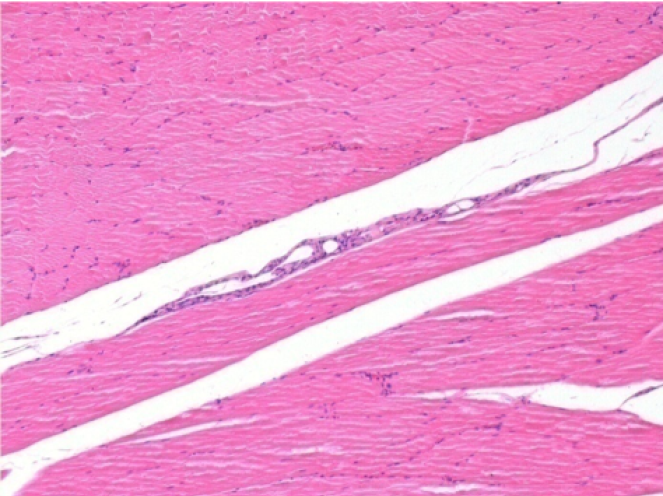

3 months after Endopeel Injection

3 months (D90)after Endopeel Injection 0.1ml in the right pretibial muscle.

L : Control-100xD90

R:100xD90